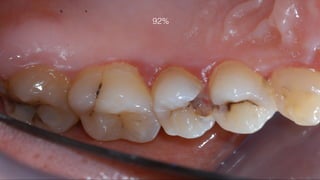

2% tooth decay 92% tooth decay

On the right is a repaired tooth

it will need repeated repairs throughout this child’s life

92%